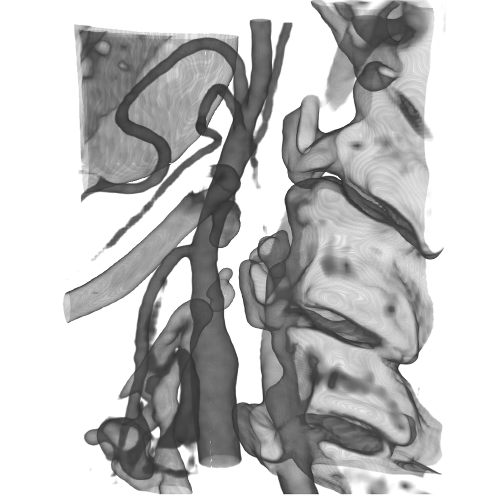

3.2 Connected Geodesic Paths as Vascular Tree

Representative examples of degraded synthetic images from SVT and the respective GT are shown in fig. 4 together with the connected graphs extracted by VTrails. Analogously, the same set of images are reported for the real images TOF and CTA in fig. 4. Qualitatively, the extracted set of connected geodesic paths shows remarkable matching with the provided GT in all cases. First, we verify the acyclic nature of the graph. We found no cycles, degenerate graphs and unconnected nodes, meaning that the extracted connected geodesic paths represent a connected geodesic tree. Precision and recall are then evaluated for the identified branches. Also, error distances are determined as the connected tree’s binary distance map evaluated at GT. Average errors () precision and recall are reported (meanSD) in table 1. Note that no pruning of any spurious branches is performed in the analysis.